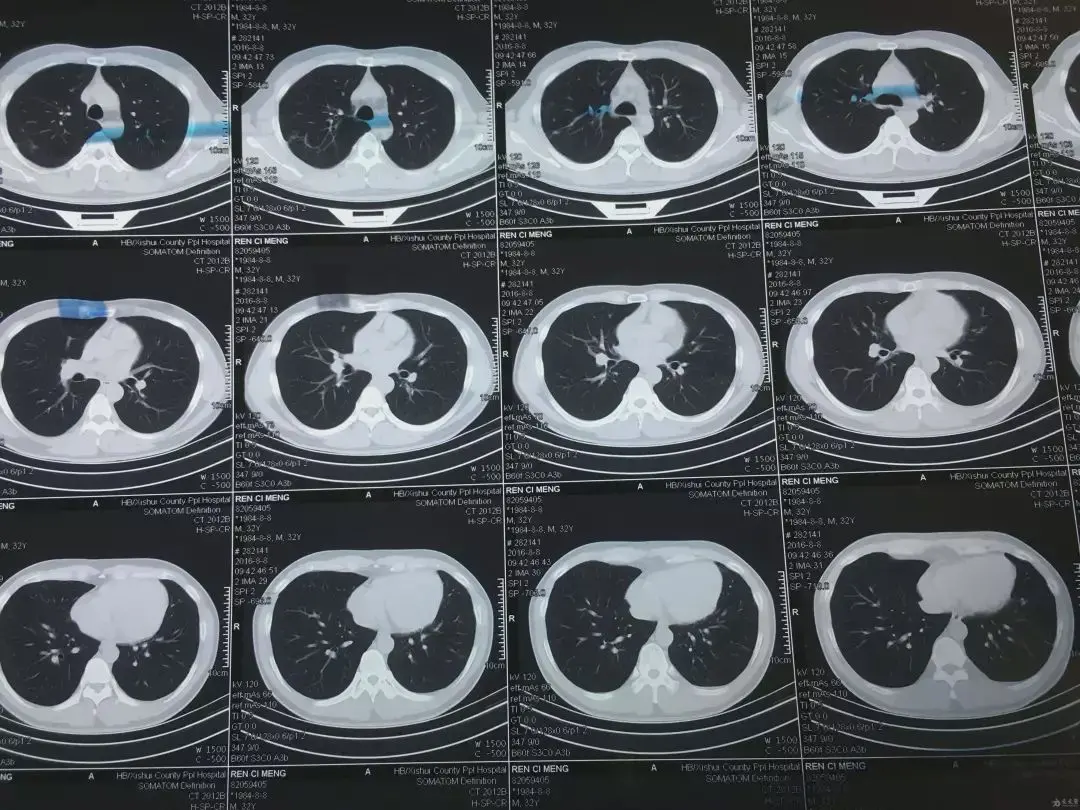

这次,他们整出了个名叫PANDA ( pancreatic cancer detection , with artificial intelligence )的 AI 大模型,根据简单的平扫 CT 图像,它就能做出胰腺癌相关的诊断。

PANDA 帮忙筛查胰腺癌的过程说起来也很简单,和医生看片子也没啥两样。

不过它凭借强大的算法,注意到的细节比医生肉眼看到的多得多,自然也能顺利找到疑似病变的地方。

PANDA 在拿到平扫 CT 图之后,先会用分割功能在整张图像中找到胰腺的位置。

找到胰腺后,再启动检测功能,去看胰腺里有没有啥不对劲的地方。

要是找到有异常的地方,就用第三步的分类功能,去识别这情况属于哪种胰腺病变。